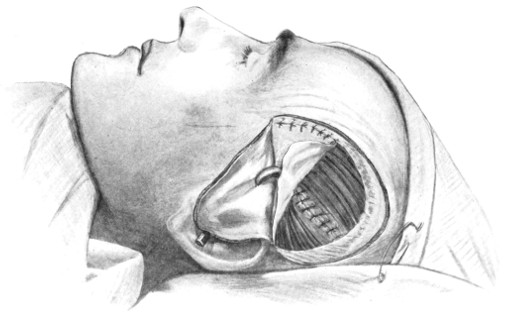

Fig. 19. Third Stage in the Formation of an Osteoplastic Flap. The dural flap turned down and the brain exposed. Note the relation of the scalp, bone, and dural incisions to one another.

In comparing the relative advantages and disadvantages of craniectomy and craniotomy, although there are certain definite contra-indications to the latter method, yet craniotomy should always be carried out when the surgeon desires to expose a large surface area of brain, more especially in the exposure of a tumour diagnosed to lie in relation to the motor cortex. Even if the operator should be unsuccessful in his exploration, or, if finding the tumour, should deem it irremovable, the dura can be sewn up and the bone-flap replaced, resting on its bevelled edge, with little defect in the skull and a normal surface contour.

The three main disadvantages to craniotomy are as follows:—(1) the operation can seldom be done under much less than thirty minutes; (2) there is some slight risk of complication through injury to the middle meningeal artery; and (3) the dura mater may be so[29] adherent to the bone as to be torn in the process of flap-elevation. Time, however, is usually of little importance; bleeding from the middle meningeal artery may be controlled, and dural lesions may be avoided by careful technique. In general, the advantages of osteoplastic resection greatly outweigh the disadvantages.

The[30] flap is replaced, care being taken that its lower or fractured edge does not injure the dura mater. The aponeurotic and subcutaneous tissues of the scalp-flap are sewn up in the manner stated on p. 16.